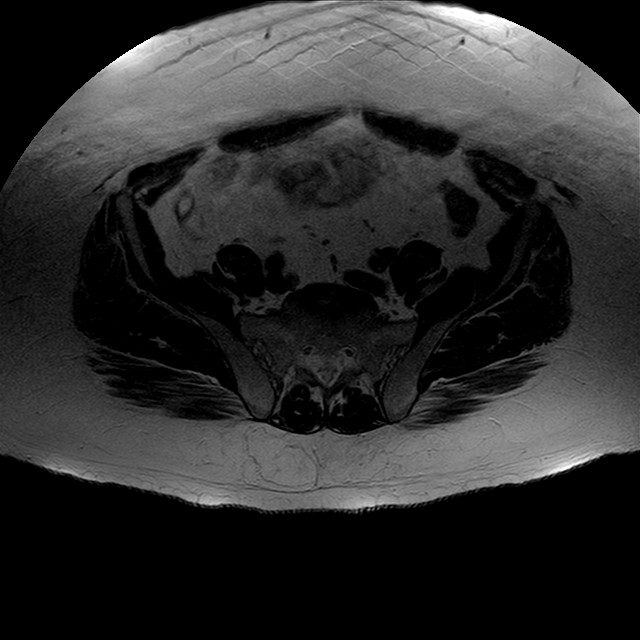

Esami: RMN BACINO

eT2w TSE

Evidenti e simmetriche alterazioni osteofitosiche in regione coxo femorale con riduzione delle rime articolari. Degenerazione completa del cercine glenoideo. Non attuali segni di versamento articolare. Non segni di edema osseo che escludono attuale algodistrofia od osteonecrosi. Lieve e simmetrica riduzione del trofismo della muscolatura glutea.